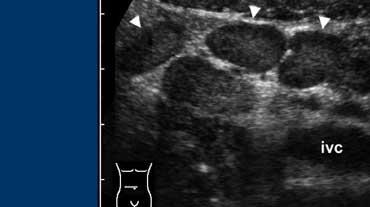

Hình 1. Tình nguyện viên khỏe mạnh 34 tuổi với ruột thừa bình thường. A và B, Siêu âm theo mặt phẳng dọc (A) và ngang (B) cho thấy ruột thừa (đầu mũi tên) có đường kính nhỏ hơn ngưỡng cắt 7 mm, được bao quanh bởi mô mỡ bình thường không viêm.

Trên siêu âm, ruột thừa bình thường ít được quan sát thấy hơn, với tỷ lệ dao động từ 0-82% [1], phản ánh sự phụ thuộc vào người thực hiện của phương pháp siêu âm.

Một trong những tiêu chí hình ảnh quan trọng nhất trong đánh giá viêm ruột thừa là đường kính ngoài của ruột thừa.

Mặc dù đã có báo cáo về sự chồng lấp đường kính ruột thừa giữa trường hợp bình thường và viêm, ngưỡng giá trị 6-7 mm được sử dụng phổ biến nhất [1]. (Hình 1).